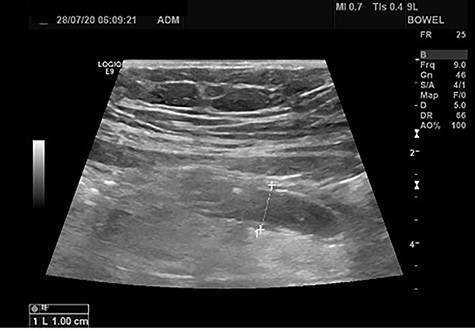

Abdominal examination disclosed deep tenderness at Mc Burney point and positive Rovsign’s sign, whereas rebound tenderness in the right iliac fossa, psoas sign and obturator sign were all negative. Laboratory studies revealed elevated white blood cells and neutrophils (white blood cell count 15.37 K/Ul and neutrophils 86.5%) with normal C—reactive protein (5 mg/l). The initial diagnosis was acute appendicitis confirmed by the ultrasonographic findings: enlarged noncompressible blind tubular structure in the right iliac fossa (diameter 1 cm) periappendiceal fat stranding. No free fluid was found (Fig. 1).

Abdominal ultrasound: The appendix is enlarged (diameter 1 cm) and non-compressible. Inflammation of the adjacent fat is also observed.